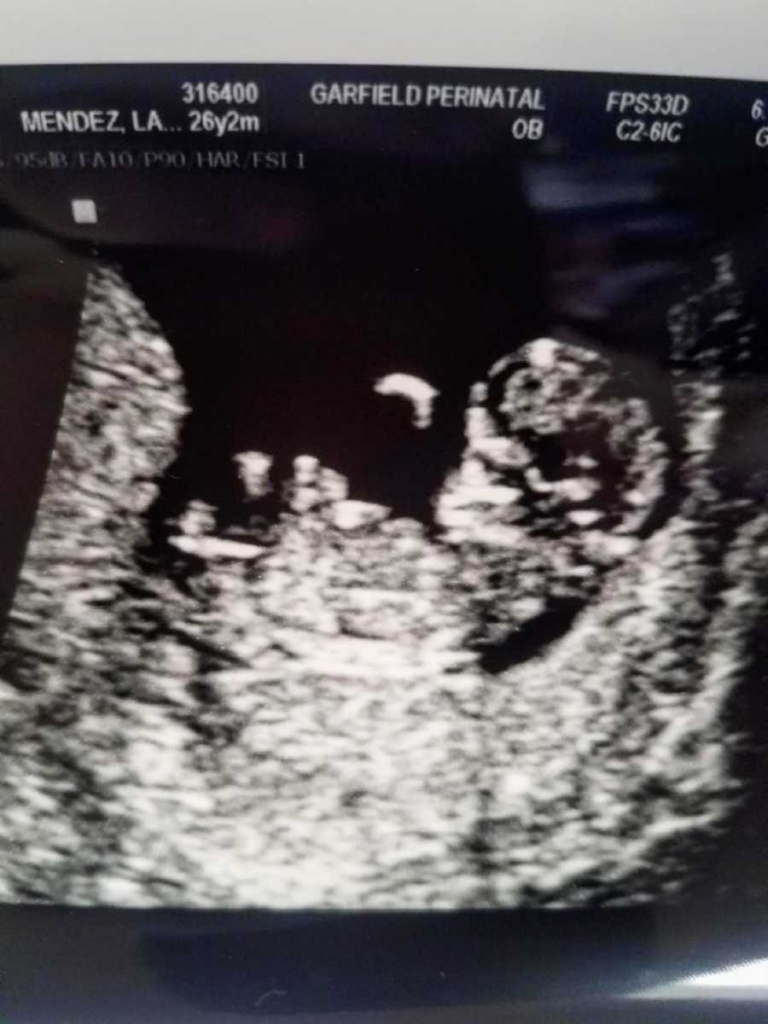

The ultrasound revealed the truth: the IUD had moved and rested within her vaginal canal. Its removal was uncomplicated and in no way threatened the baby. This was a huge sigh of relief after weeks of living in fear. Laura had been warned not to bond with him. She lived with unresolved uncertainty, preparing for the worst. Prenatal care did not improve. Appointments were either rushed or canceled. At twenty weeks, her doctor mentioned that he hadn’t thought the pregnancy would have lasted this long. Persistent pelvic pain was left unexplained until a visit to the hospital determined round ligament pain. Many of Laura’s questions remained unanswered. Laura shares her story not out of anger for what has happened to her, but out of love for her son and in grief for the experience she never fully had.